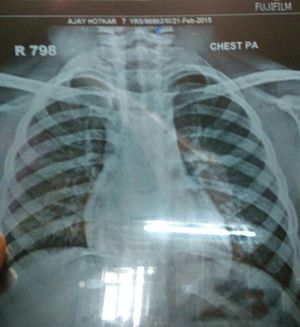

Diagnosis of Xray??

Xray

Peadiatric

Chest X-Rays